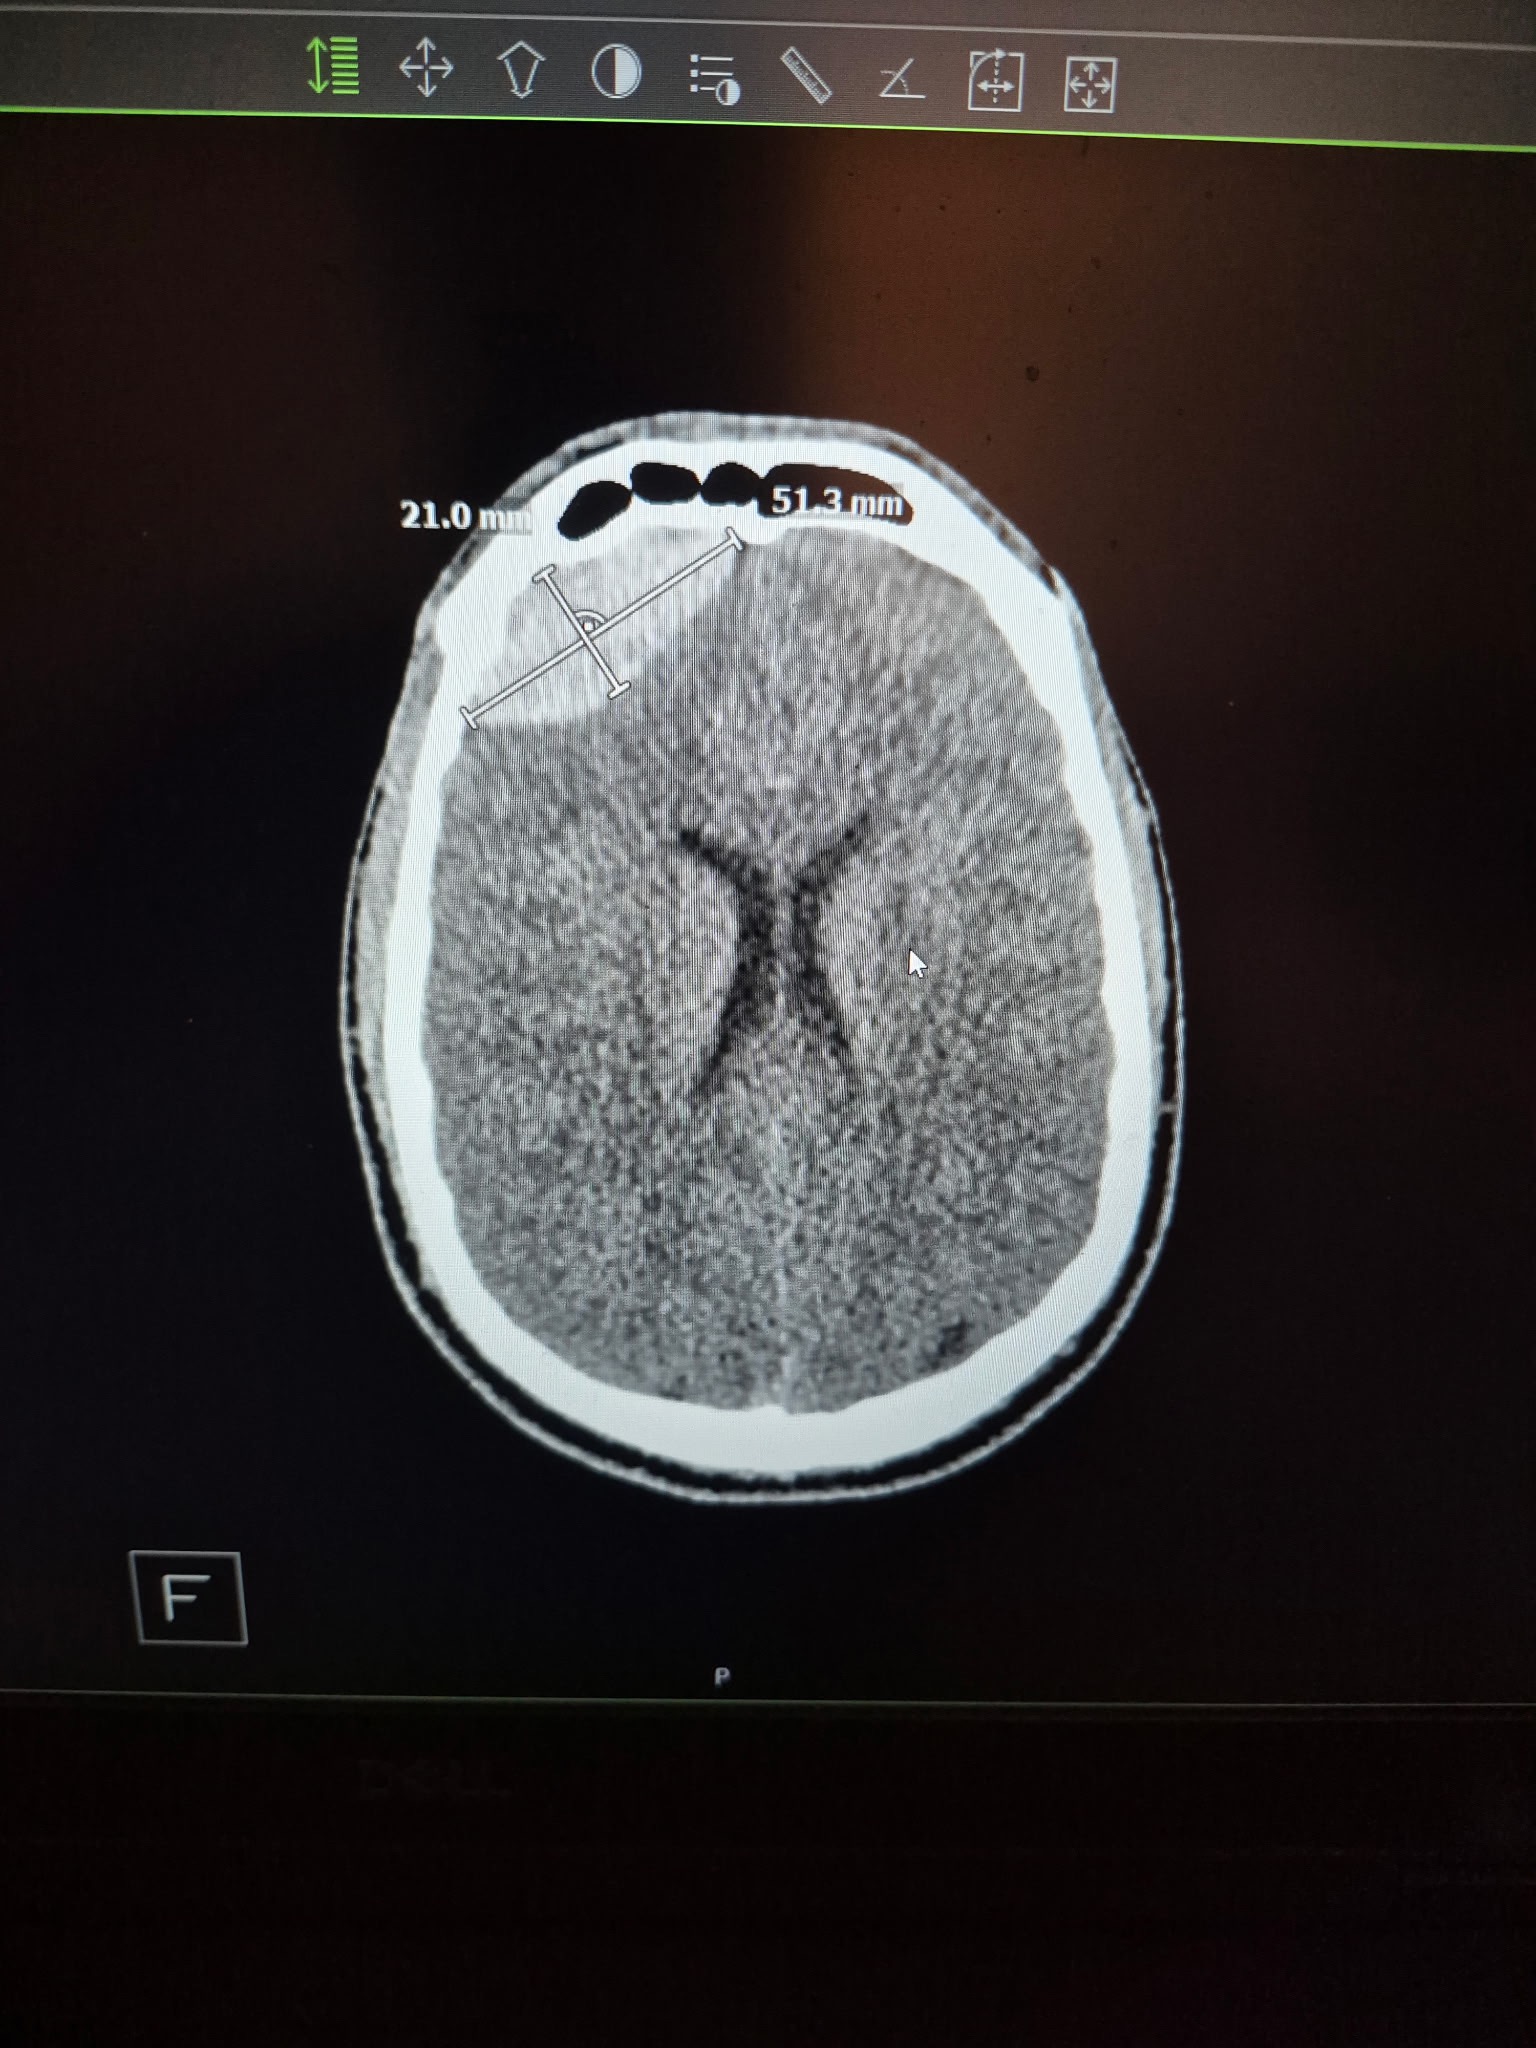

He had an epidural hematoma which required a craniotomy, a broken sternum, around 5 broken ribs, multiple broken cervical and thoracic vertebrae requiring a T1-T8 spinal fusion, and a long hospital stay.